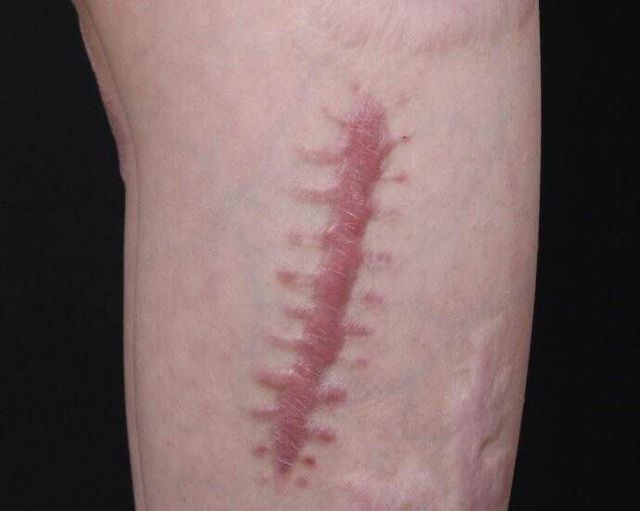

任何人:就诊费也很高,做手术从不留疤,也可以植皮手术,这样她的疤痕就消失了

上官夜(父):找到的时候受了一些伤,胳膊上缝了十几针,留疤了

#慕容海(大哥):我能看看我妹妹的伤吗?我先做个总结,到时候我在研究怎么手术方案

千田灵子(冷母):嗯

千田灵子(冷母):说完走向床边把被子往下拉了一下吧胳膊拿出来

慕容雪凝:

作者希沫:不要在意细节,只看伤疤

#慕容海(大哥):当看到妹妹手臂上的疤痕时,就心疼的落了眼泪

#慕容海(大哥):妹妹还这么小,怎么会伤的那么严重